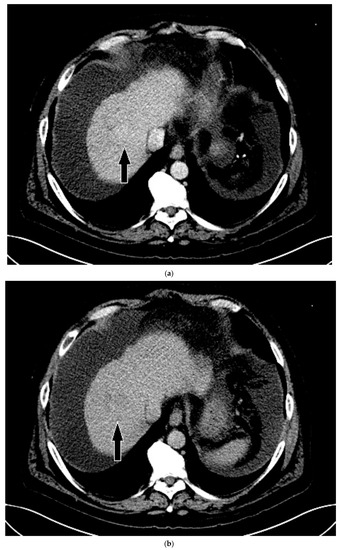

On grayscale imaging, a 2.9 cm hypoechoic lesion at the dome of the right lobe on a background of heterogeneous liver parenchyma was identified (Figure 5). Due to his acute on chronic renal failure, CEUS was then performed, which showed subtle enhancement of the lesion, above background enhancement of the adjacent liver at the same depth. At or greater than 10 cm depth is most often the limit of penetration in standard CEUS software packages [13], but can be extended in the presence of ascites, as in our case. Subtle washout was identified on delayed imaging, and the lesion was deemed LI-RADS 5 (Figure 5).

Figure 5.

Patient 3 ultrasound images, ascites is present with lesion denoted by white arrow: (a) grayscale images showing the hypoechoic lesion. Post contrast administration ultrasound in arterial phase shows subtle enhancement compared with liver parenchyma at the same level (b) and delayed phase mild washout (c) of the lesion, LI-RADS 5.

His liver function continued to decline during his stay, and within two weeks he received a deceased donor liver transplantation. HCC within the explanted liver was confirmed by histopathological examination, corresponding to the findings on CEUS. Upon review of the prior CT, for which a reduced contrast bolus (75 mL Omnipaque™ 350) was given due to his chronic renal disease, the tumor was subtle but faintly visible with the knowledge of its location based on the findings on CEUS (Figure 6).